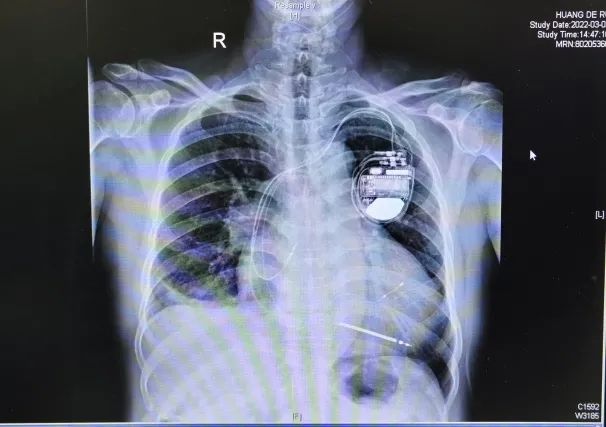

手术当日,在局部麻醉下,陈林教授团队将两根电极依次放入右心房、右心室,并用娴熟精湛的技巧,将最后一根电极精准放入弯绕的冠状静脉侧支血管,用时2个多小时即顺利植入最新仪器,患者各项参数检测正常,原先心电图QRS波宽度由208ms缩短至138ms。

▲患者植入3T MRI CRTD后的CT图